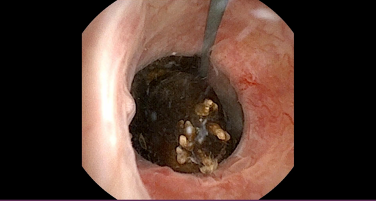

Finally, there is the active destruction or removal of stones. This can be done using extracorporeal shockwave lithotripsy (ESWL) or surgery (Figure 3A). ESWL is suitable in stones that are <2cm in size. It is usually done with the patient awake and involves using sound waves to fragment the stones, which can then be passed out in the urine. It may require more than one session to fragment the stone.

More invasive surgical approaches are usually done by the minimally-invasive endoscopic approach known as ureteroscopy. This involves passing a semi-rigid or flexible scope via the urethra to the ureter and renal pelvis. Through this scope a laser and other instruments can be passed, which allows destruction and extraction of stones (Figure 3B & 4). This can usually be done as a day case procedure under general anaesthesia and is suitable for most stone types.

FIGURE 3: Options for active stone management or destruction: A demonstrates ESWL; B flexible ureterorenoscopy; and C PCNL (All images courtesy of EAU Uroweb)